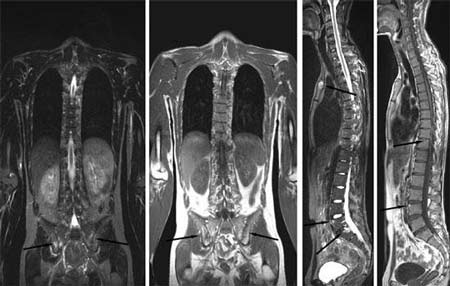

X线片:患者骶髂关节骨质受损,关节间隙可见狭窄,关节边缘毛糙。脊柱有两处关节变形迹象。

(图:患者入院时X片显示,骶髂关节受损、脊柱关节变形弯曲)

经过三个疗程的治疗后,患者骶髂及颈椎关节无疼痛现象,晨僵消失,经实验室检查显示,患者各项指标均恢复正常,X片显示患者脊柱关节已无变形迹象,全身各关节可自由活动。